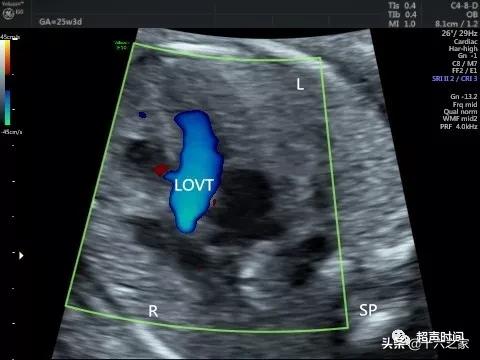

图 6 胎儿左室流出道切面未见明显异常